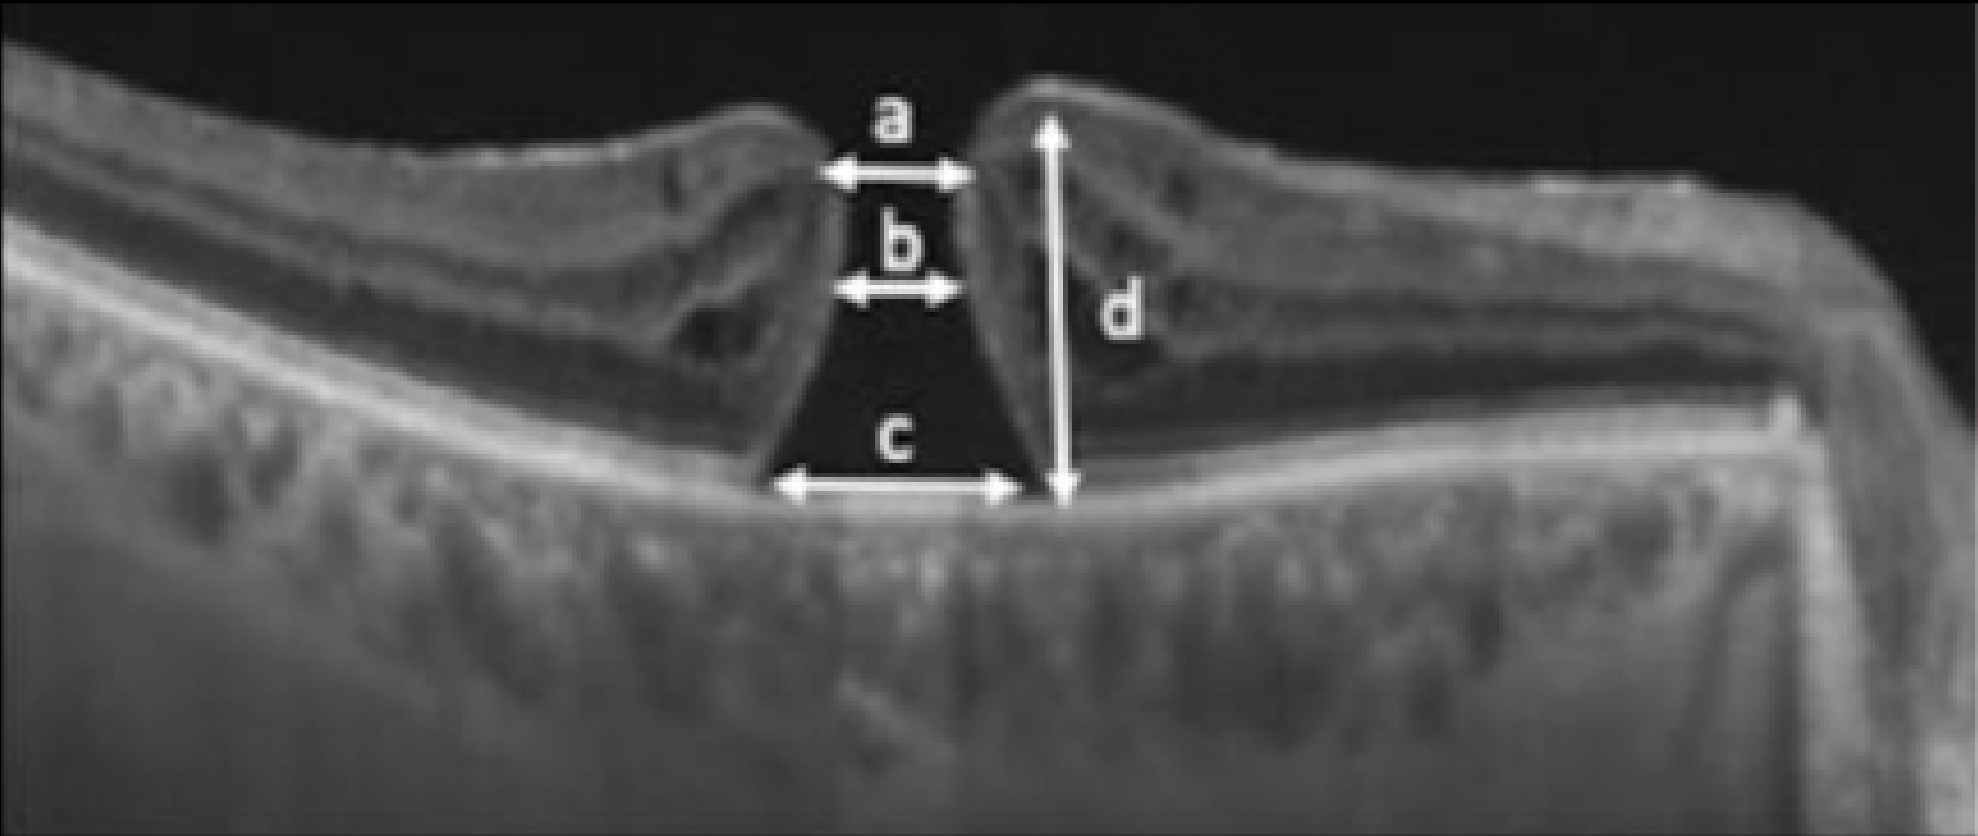

Exclusion criteria included presence of retinal dystrophy, foveoschisis, neovascular age-related macular degeneration and history of vitreous surgery less than one year prior. SD-OCT scans were reviewed for macular parameters including apical diameter, narrowest diameter, basal diameter and height (Figure 1).

Figure 1. A diagram of full-thickness macular hole parameters: a = apical diameter; b = minimum diameter; c = basal diameter; and d = height. (Reprinted with permission from Uwaydat SH, Mansour A, Ascaso FJ, et al. Clinical characteristics of full thickness macular holes that closed without surgery. Br J Ophthalmol. 2022;106:1463–1468.)3 |

Additional FTMH parameters that we evaluated include macular hole index (height/basal diameter), diameter hole index (DHI, an indicator of tangential traction defined as narrowest diameter divided by basal diameter), tractional hole index (THI, an indicator of anteroposterior traction and retinal hydration defined as height/narrowest diameter) and subretinal fluid volume.